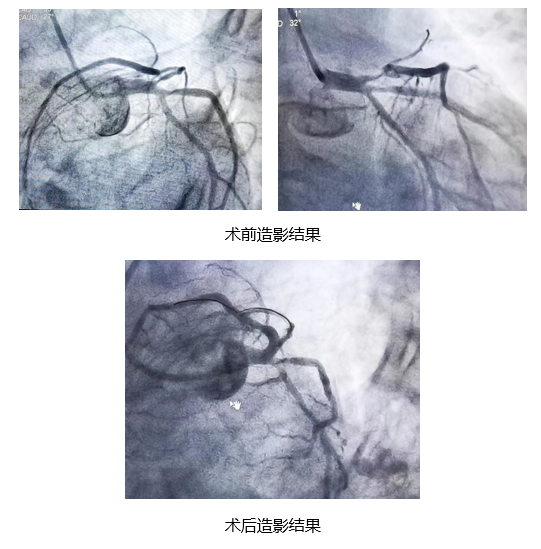

接诊医师发现这位没有家属陪同的患者是我院内分泌科护士张芳芳的爱人,而她此刻正在拉萨执行援藏任务。此时急诊造影结果显示前降支开口部位95%~99%狭窄,呈次全闭塞状态,病势十分凶险,有随时猝死的可能。我院迅速开通绿色通道,将患者送入介入室。

心血管科迅速行动,刘红旭主任带领介入团队周琦副主任医师、李腾飞主治医师开始手术,为患者开通血管,精确定位植入支架,患者病情迅速得到缓解,血流动力学稳定,生命体征平稳,DTOW(从患者进入医院大门到导丝通过)时间仅用了47分钟。手术顺利完成后,刘红旭主任与正在援藏一线的张芳芳联系报平安。